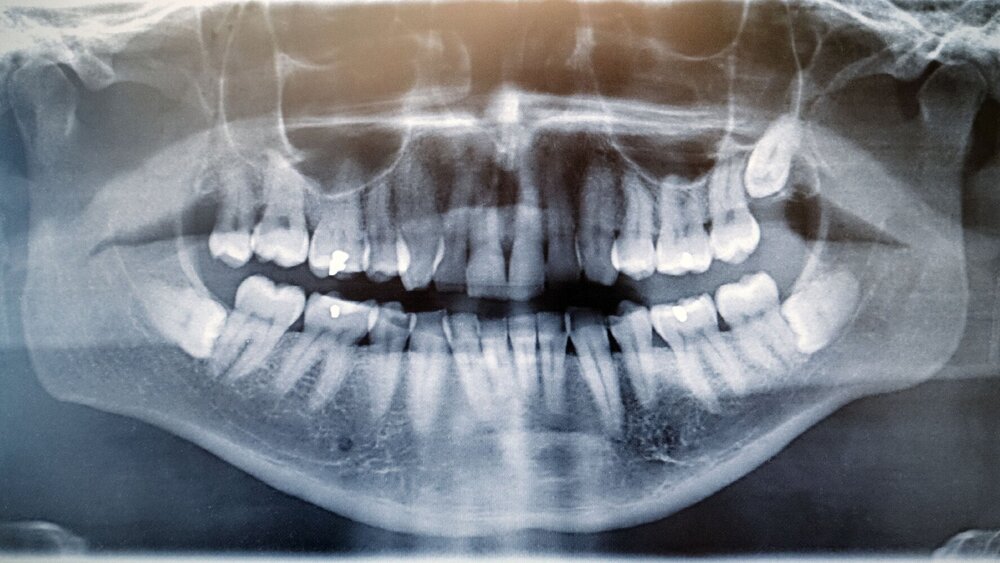

Gaben die Patienten bei Nahtentfernung sieben Tage postoperativ neurosensorische Defizite an, wurden Test zur Objektivierung durchgeführt (Light-Touch-Test, Zwei-Punkt-Diskriminationsschwelle, Nadelstichtest, Vitalitätstest der ipsilateralen Unterkieferzähne). Eine abschließende Bewertung fand nach 12 Monaten statt. Blieben die Defizite bis dahin bestehen, wurden diese als dauerhaft klassifiziert. Mithilfe von Panoramaschichtaufnahmen und DVTs (bei 47,2 Prozent der Operationen) wurde die Lage des impaktierten Zahnes sowie die Lagebeziehung der Wurzeln zum N. alveolaris inferior bewertet (apical, bukkal, lingual, interradikulär).

Insgesamt wurden Daten von 418 Patientinnen und Patienten beziehungsweise 555 Weisheitszähnen eingeschlossen. Rund 29 Prozent der Operationen wurden von Zahnmedizinstudierenden unter Aufsicht durchgeführt, alle weiteren von Zahnärzten beziehungsweise Kieferchirurgen. 39,1 Prozent aller Zähne zeigten eine mesioanguläre, 26,7 Prozent eine horizontale, 18,2 Prozent eine distoanguläre und 14,4 Prozent eine vertikale Impaktion. Von den 263 Zähnen, von denen ein DVT angefertigt wurde, hatten 84 Prozent Kontakt mit dem N. alveolaris inferior. Dabei befand sich der Nerv zu 27 Prozent apical, zu 30,8 Prozent bukkal, zu 35,4 Prozent lingual sowie zu 6,9 Prozent interradikulär der Zahnwurzeln.